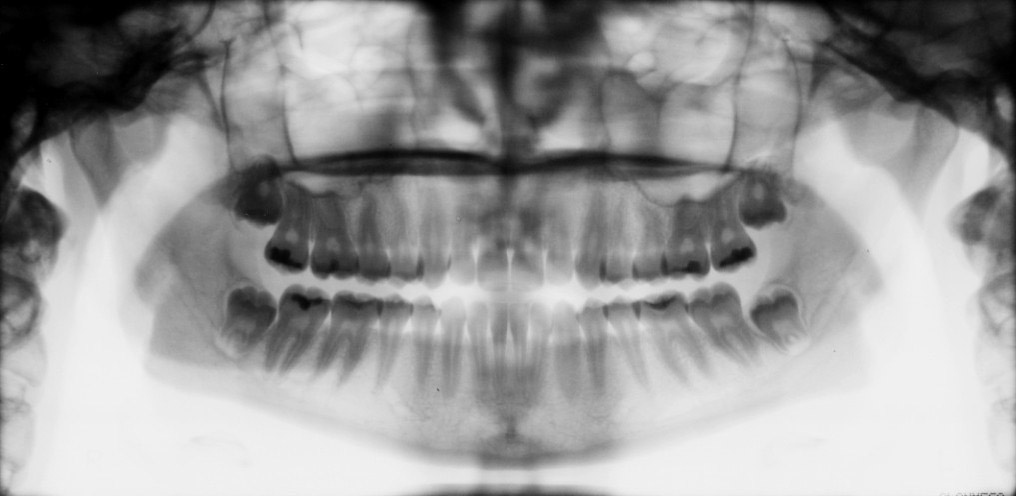

Figure 3. One of the steps in digital imaging is to create a patient file in the computer software to acquire and archive radiographic images. In this example, a bitewing template was selected, and then the images were captured and displayed on the monitor. (Patterson Dental Supply, Inc)

Figure 3

Infection Control—Typically, the receptor instruments can tolerate sterilization methods such as steam autoclaving before reuse. Digital receptors cannot be sterilized so the clinician must adhere to careful disinfection and barrier coverage techniques to avoid direct and cross-contamination of the receptor. The standard spray-wipe-spray or immersion disinfection technique is not appropriate for sensor preparation. Wiping rigid digital sensors with a mild disinfectant agent before barrier placement is thought to be an acceptable disinfection practice.25 When in doubt, refer to the manufacturer’s instructions regarding recommendations for sensor preparation and protection prior to use. PSP plates should be inserted into a barrier envelope and sealed before placement in the mouth. After removal, the barrier should be cleaned with disinfectant hand soap and water and then dried.26 Following glove removal and hand washing, the barrier should be opened carefully and the plate dropped out with the sensitive side down into transfer carrier.26 The clinician should be observant during the radiographic procedures to ensure that the barrier does not become torn during instrumentation. Table 1 presents the basic steps involved in intraoral digital imaging. An example of a patient file is depicted in Figure 3. The act of saving the image is similar to saving any file on a computer system.